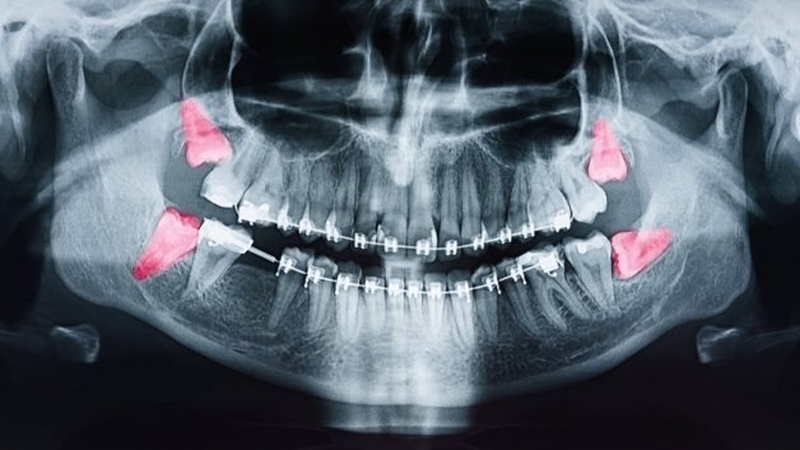

Răng khôn là những chiếc răng cuối cùng mọc lên ở phía sau nướu. Hầu hết mọi người có 4 chiếc răng khôn (1 chiếc ở mỗi góc), thường mọc ra từ 18 đến 25 tuổi, rất hiếm người không mọc răng khôn. Tuy nhiên, vì không phải lúc nào trong miệng cũng có đủ chỗ cho răng khôn mọc đúng cách, nên chúng có thể gây ra các vấn đề như mọc lệch, bị kẹt, nhiễm trùng, gây tổn thương các răng lân cận hoặc bệnh nha chu.

Việc loại bỏ răng khôn là cần thiết nếu gặp phải các vấn đề như đau đớn, nhiễm trùng, sưng mủ, khối u, tổn thương các răng lân cận, bệnh nướu răng hoặc sâu răng trên diện rộng. Nếu răng khôn bị va đập hoặc chưa đâm xuyên qua bề mặt nướu có thể gây ra các vấn đề về răng miệng. Việc nhổ răng khôn nên được thực hiện ở độ tuổi càng sớm càng tốt để giúp bạn hồi phục nhanh hơn.

Răng khôn, còn được gọi là răng số 8, là chiếc răng nằm cuối cùng của cung hàm và thường mọc muộn nhất trong tất cả các răng. Tuy nhiên, do tính chất mọc trễ, răng khôn thường mọc lệch hoặc ngầm, gây ra nhiều biến chứng cho cơ thể. Vì vậy, bác sĩ thường khuyên người bệnh nên nhổ răng khôn sớm để tránh tình trạng này.